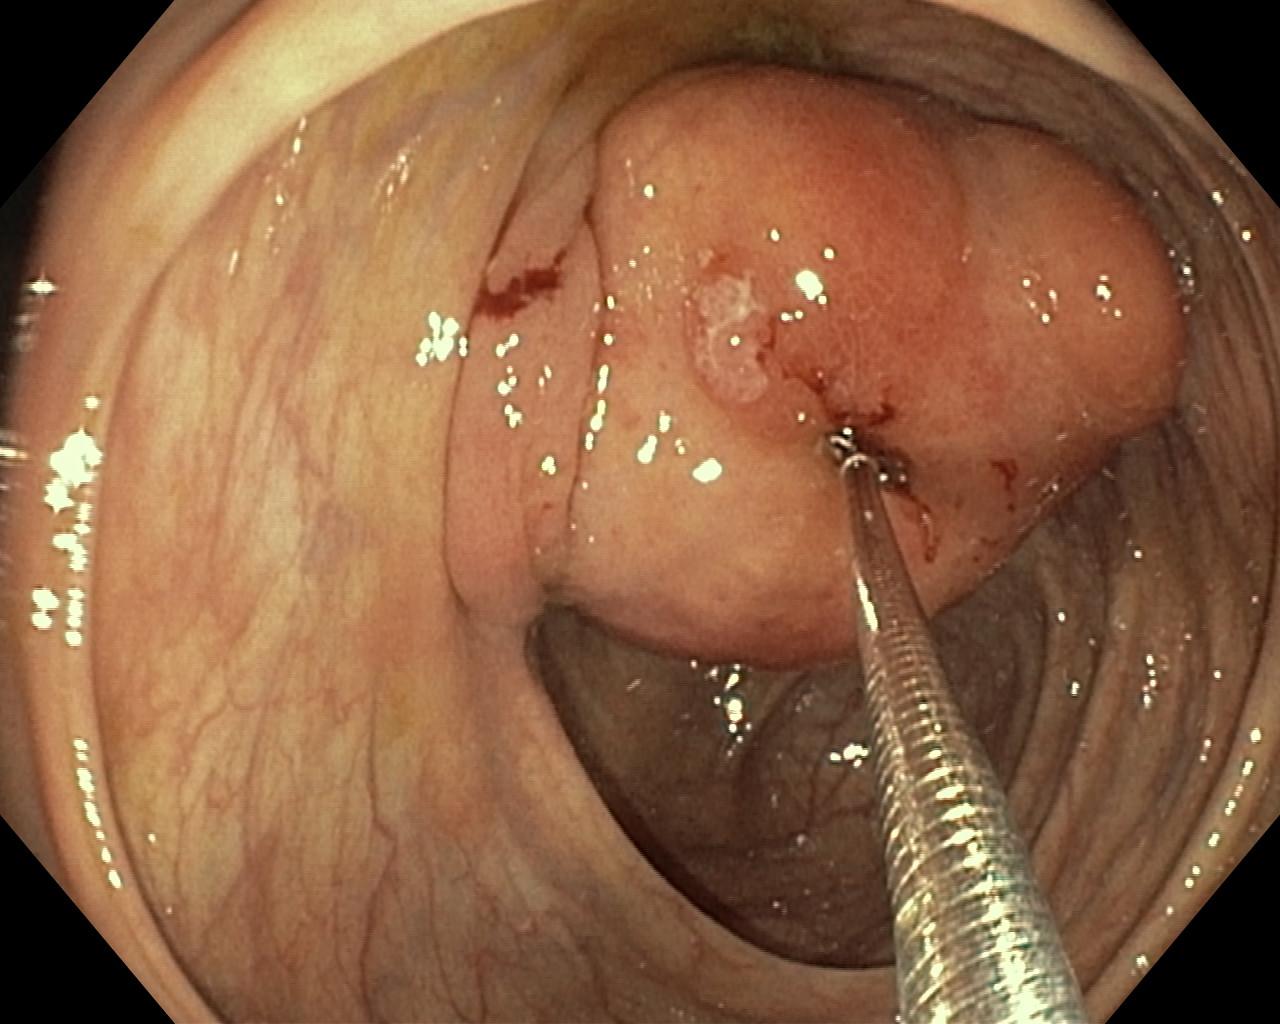

Nowotwory przewodu pokarmowego

Zabiegi endoskopowe